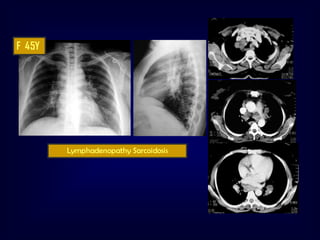

Sarcoidosis

•

Multi system granulomatous disease

• Unknown etiology

90% of patients with sarcoidosis have

chest changes

Bilateral hilar and mediastinal adopathy

Interstitial disease  lymph nodes

Alveolar pattern simulating acute

inflammatory disease]

Cavitation, atelectasis, effusion (rare)

Nodal and Interstitial patterns

F 45Y

Lymphadenopathy Sarcoidosis